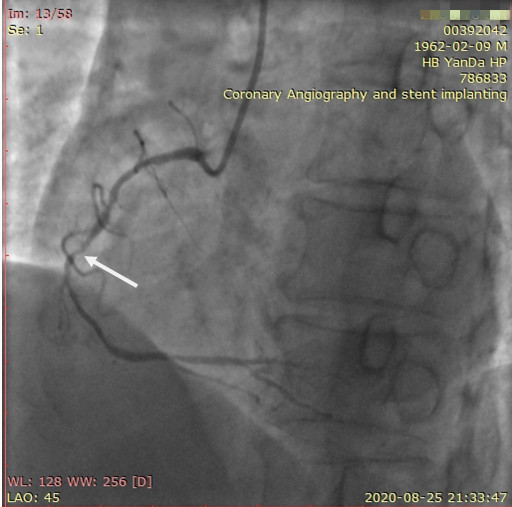

近日,河北醫(yī)科大學(xué)附屬燕達(dá)醫(yī)院心血管內(nèi)三科成功完成一例非常特殊的手術(shù)——冠心病三支病變微創(chuàng)介入完全血運(yùn)重建術(shù)?;颊呃钕壬谛牟〔∽儤O其嚴(yán)重,全部三支主干動(dòng)脈均重度狹窄,各處求診均被告知無(wú)法微創(chuàng)介入手術(shù),只能開(kāi)胸搭橋。拒絕開(kāi)胸的李先生慕燕達(dá)醫(yī)院心血管內(nèi)三科北京安貞醫(yī)院專家團(tuán)隊(duì)之名,就診于燕達(dá)醫(yī)院,由翟光耀主任為其行 “一站式”手術(shù),一 次 性完成三支動(dòng)脈的修復(fù)!手術(shù)非常成功,李先生術(shù)后恢復(fù)良好,滿意出院。

58歲的山西男性患者李先生,3年來(lái)頻繁發(fā)作心絞痛,程度、頻率逐漸增加。曾就診于當(dāng)?shù)蒯t(yī)院,冠脈CTA及冠脈造影結(jié)果,均提示:患者三支血管病變嚴(yán)重,病情復(fù)雜,血管不但鈣化嚴(yán)重,還有90-99%的重度狹窄,微創(chuàng)介入植入支架難以實(shí)現(xiàn),建議去北京??漆t(yī)院做開(kāi)胸搭橋手術(shù)。

李先生右冠術(shù)前影像

李先生右冠術(shù)后影像

近3年來(lái),李先生曾攜帶影像資料奔走于北京各大醫(yī)院,均建議其行心外科搭橋手術(shù),但李先生考慮自身年齡、瘦弱體質(zhì)等多方面因素,堅(jiān)決拒絕。到處求診的三年,病情也拖了三年,致使癥狀不斷加重!李先生得知燕達(dá)醫(yī)院心血管內(nèi)三科北京安貞醫(yī)院專家團(tuán)隊(duì)擅長(zhǎng)復(fù)雜冠心病的“降階梯”微創(chuàng)介入治療,一路艱辛,慕名求診。

術(shù)前,翟光耀主任還親自為李先生復(fù)查冠狀動(dòng)脈造影,造影結(jié)果顯示:患者的前降支、回旋支、右冠等冠脈三支嚴(yán)重病變、嚴(yán)重鈣化,且均為彌漫性長(zhǎng)病變,最重處99%以上管腔極嚴(yán)重狹窄。翟主任仔細(xì)閱讀造影結(jié)果后指出:結(jié)合李先生的實(shí)際情況,雖然微創(chuàng)介入手術(shù)難度比較大,但仍可行;李先生心臟三支主干動(dòng)脈均存在極其嚴(yán)重的狹窄,每一支動(dòng)脈均至少植入2-3枚支架,根據(jù)患者的耐受情況,李先生可能需要分3次分別對(duì)三支動(dòng)脈進(jìn)行介入手術(shù);考慮到李先生路途遙遠(yuǎn),病情嚴(yán)重,不宜反復(fù)奔波,并且患者迫切要求能夠徹 底解決病痛,在病情允許的情況下,如果手術(shù)順利,爭(zhēng)取為患者進(jìn)行“一站式”手術(shù),一 次 性解決全部三支動(dòng)脈病變!